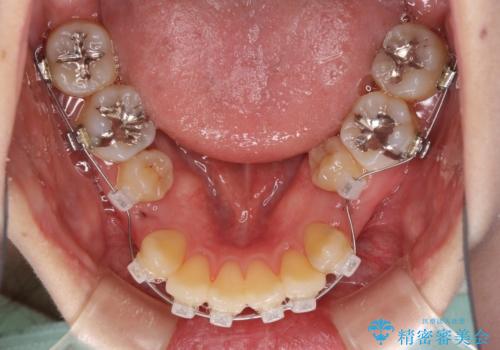

- 矯正装置

- クリアブラケット

- 下顎の歯が舌側に倒れていることと、前歯の咬み合わせの不具合を気にして来院された患者様です。

受け口傾向の口元であるため、下顎左右小臼歯各1歯を抜歯して歯列を整えることとしました。

前歯には治療中の仮歯が装着されていたため、矯正治療後にオールセラミッククラウンにて補綴治療を行うこととしました。